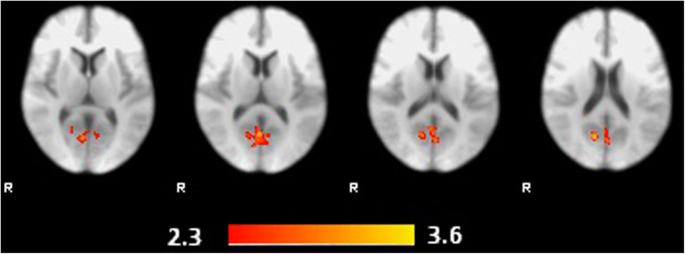

Neurocognitive Mechanisms Underlying Improvement Of Prosocial Responses By A Novel Implicit Compassion Promotion Task Sciencedirect